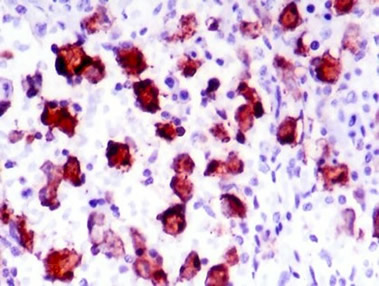

The Coccidia is also known in its initial state as an Oocysts (pronounced o'o-sists), which can easily be visualized as a little “o” inside of a big “O” as seen through the microscopic picture below. Coccidia are spread through fecal matter. Such infected fecal matter is easily passed through contact with other animals or the areas they habitate. Squirrels, birds, people’s shoes, hands, car tires and even the rain itself may spread it. Coccidia can even be spread by an infected mouse, which is then eaten by a pet and then leads to its infection. Because this illness can contaminate the cleanest environment it is important to always be on the lookout for it and treat all pets especially the very young at the first sign any infection has occurred. Because Coccidia is only visible through microscopic evaluation and its symptoms can often mimic that of other diseases such as Parvo and Distemper the illness is often misdiagnosed. The only real verification of this very prevalent illness is through fecal exam under a microscope. Because the fecal exam is much easier and cost efficient it is often the first thing that should be considered when a pet is exhibiting any of the below symptoms. The symptoms of Coccidia range from none at all to nausea, lethargy, depression and diarrhea, which is often watery and may contain blood. Because its symptoms are much the same as Parvo and other illnesses that cause dehydration the course of treatment is often the same with the addition of the special drugs Albon or another similar sulfa medication to help with the condition. An anti nausea/vomiting drug is often also provided. Anti-nausea/vomiting drugs are widely used with any condition where vomiting is a threat. Vomiting can cause great stress to a young pup and can lead to severe depression and less will to live. It is most important to treat vomiting as a critical issue. Severe vomiting can lead to rapid dehydration. Severe dehydration is the actual killer and not the disease itself in many cases where death from illness occurs. Understanding the signs of dehydration and immediately acting on its reversal can significantly improve the odds of that pet’s survival. Such action may involve something as easy as providing a moisture rich food to syringe feed and watering all the way up to IV Fluid treatment. It is important to note that Coccidia cannot be cured by the drugs that are used, but instead that these drugs inhibit the parasites growth and aid in its expulsion from the pet’s system. With fewer Coccidia in the digestive tract the pet’s immune system then is allowed to catch up and complete the task to kill the remaining. On the positive side of a pet’s infection with Coccidia, like Parvo if a dog is unlucky enough to have caught it but yet survives it will then likely gain a lifetime of immunity from future episodes.